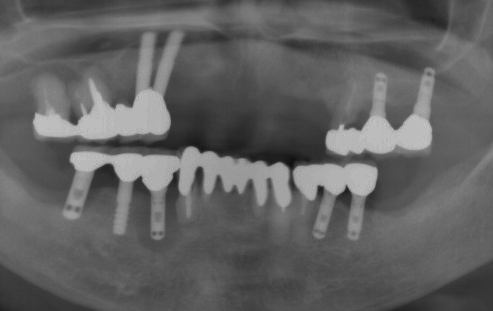

他医院でのインプラント症例 2013年

他の歯科医院で2種類のインプラントが植立してありますが、

表面がそぞうであるインプラントは、感染して骨の吸収が著しく

表面が滑沢なインプラントは感染していない。